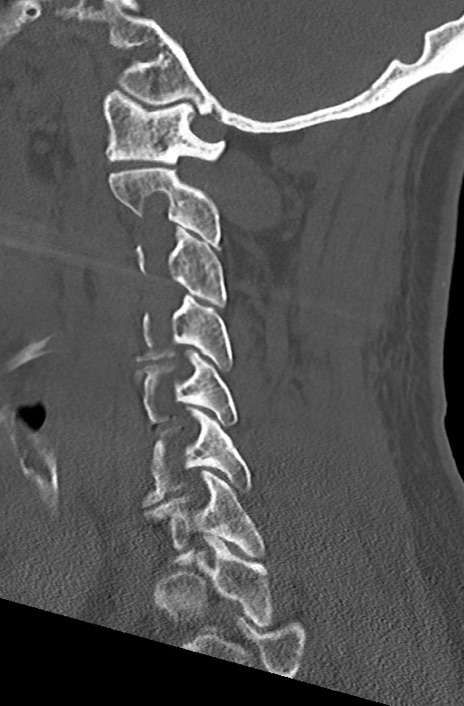

【整形】TIPS症例7 頚椎CT(矢状断像)

頚椎CT